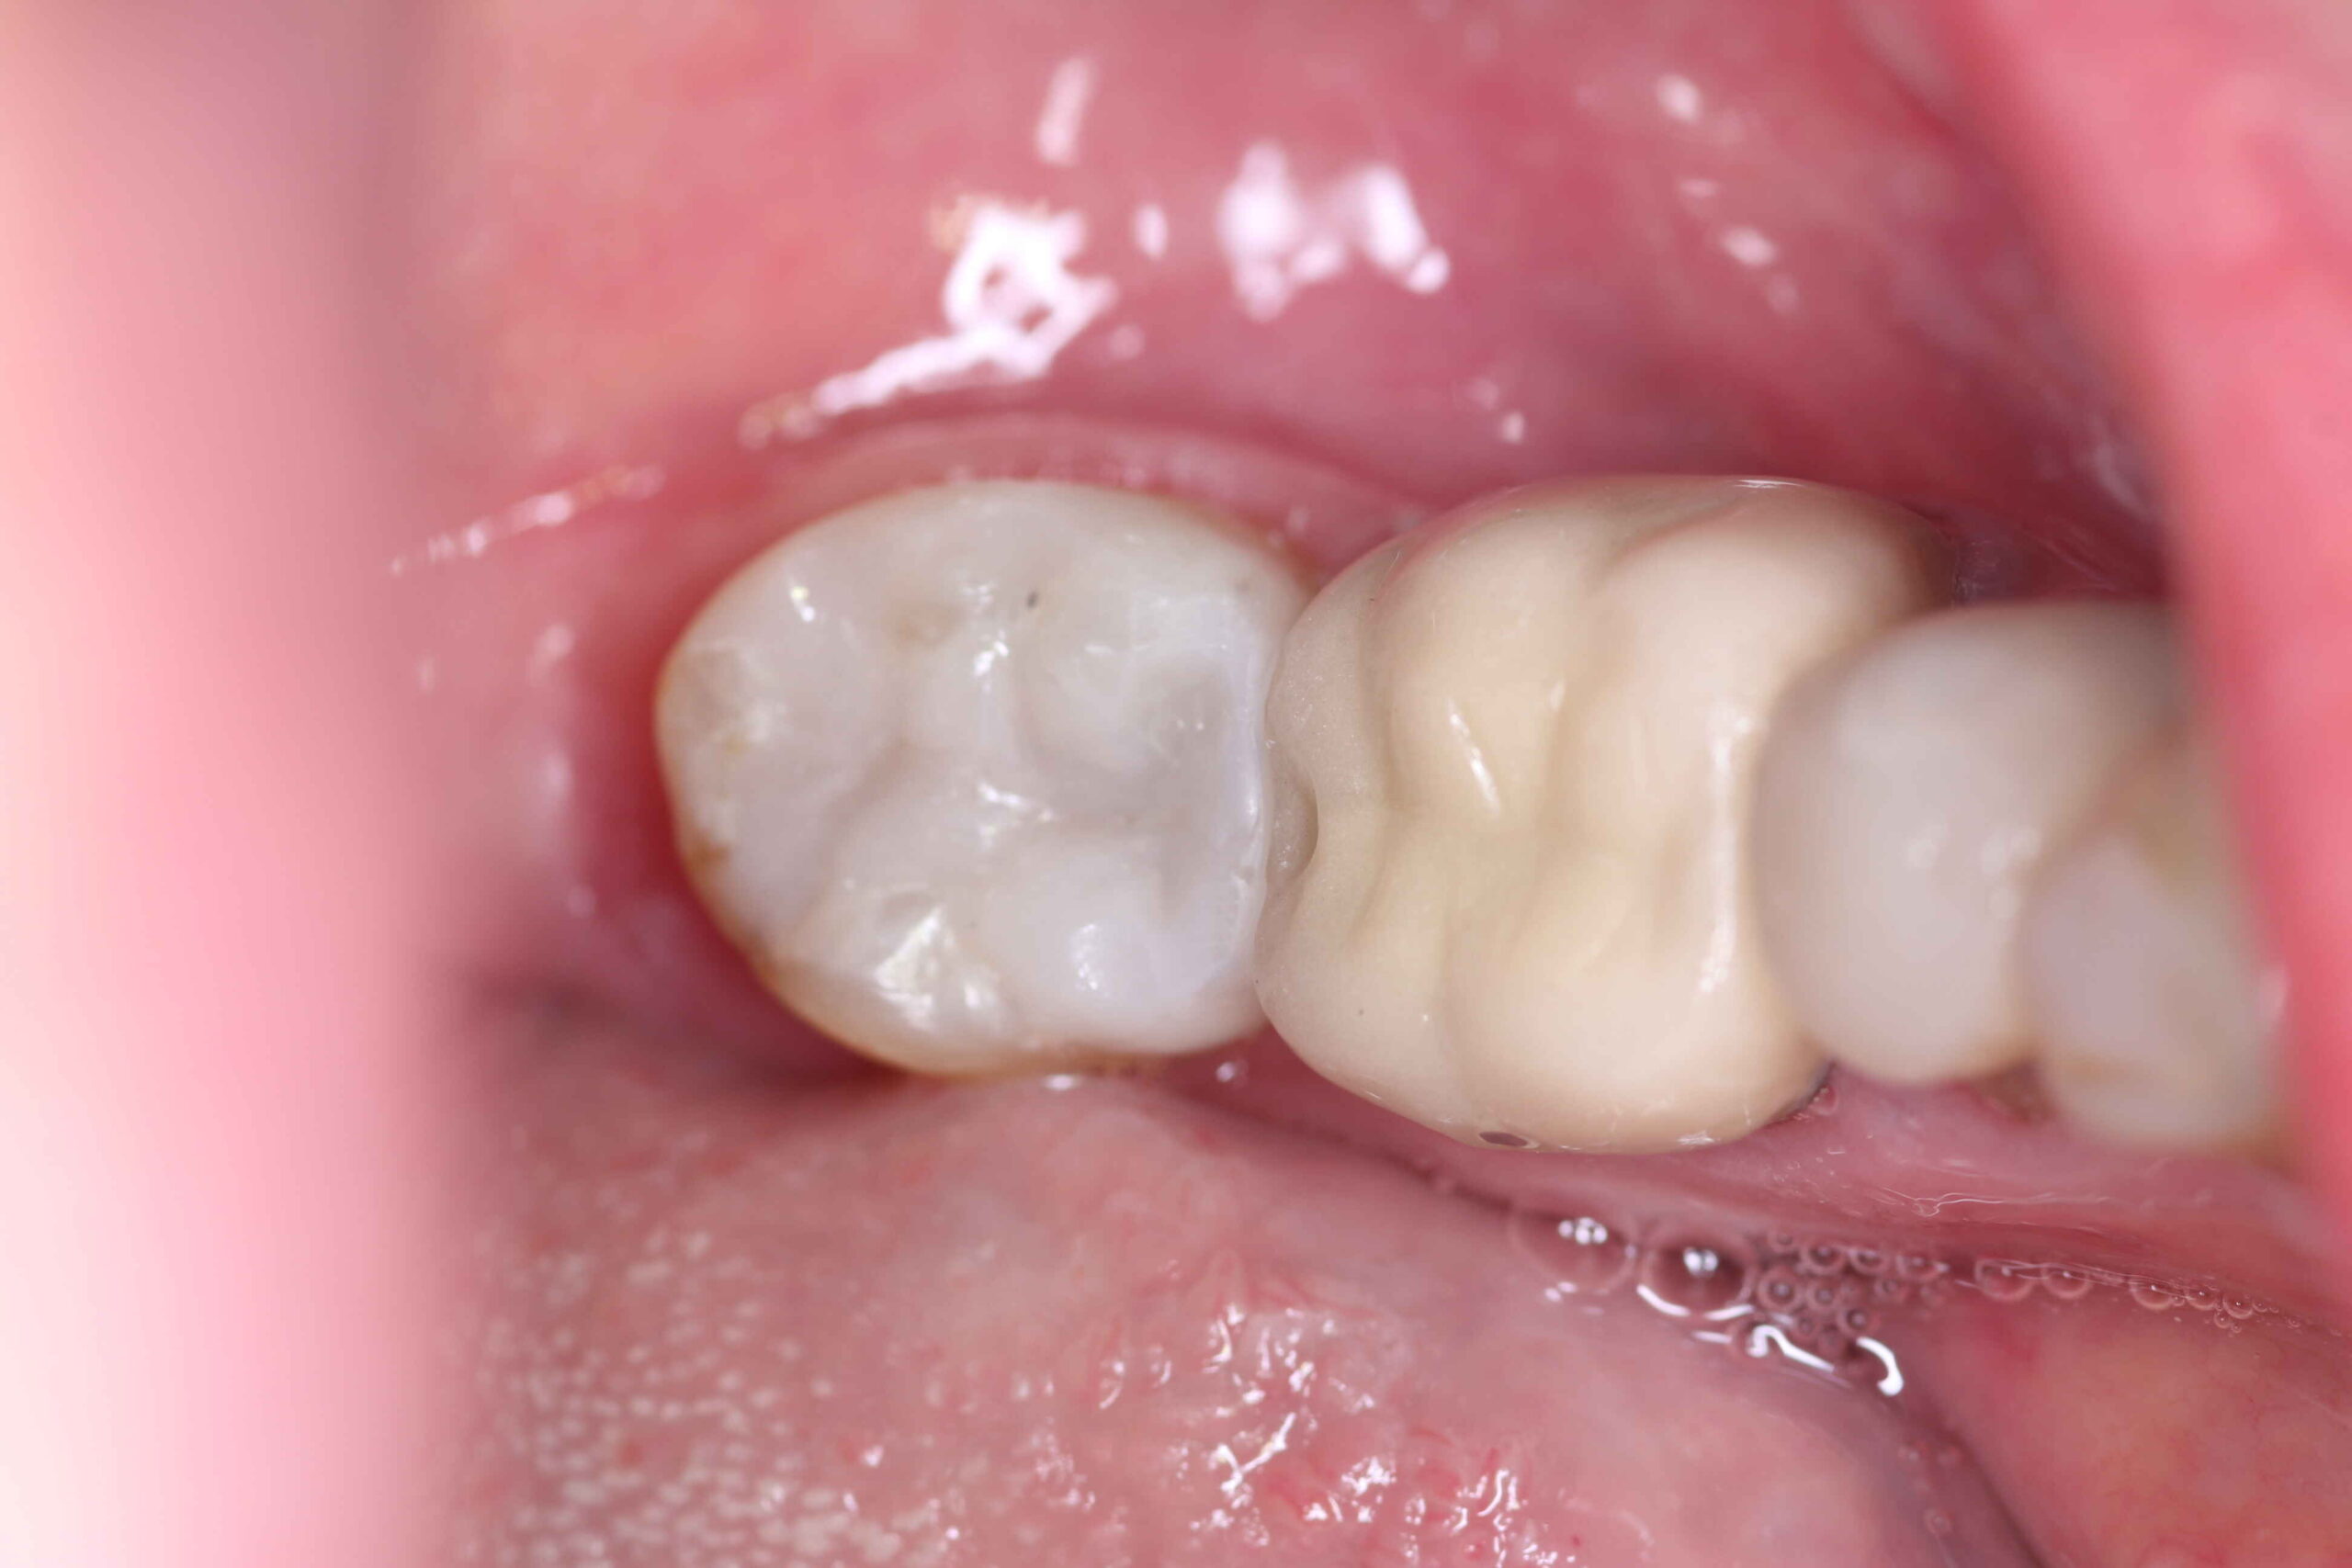

✔️ Proporciona um resultado mais estético (cor semelhante ao dente)

✔️ Preserva mais a estrutura dental

✔️ Reduz o risco de trincas e fraturas

✔️ Oferece maior adesão ao dente